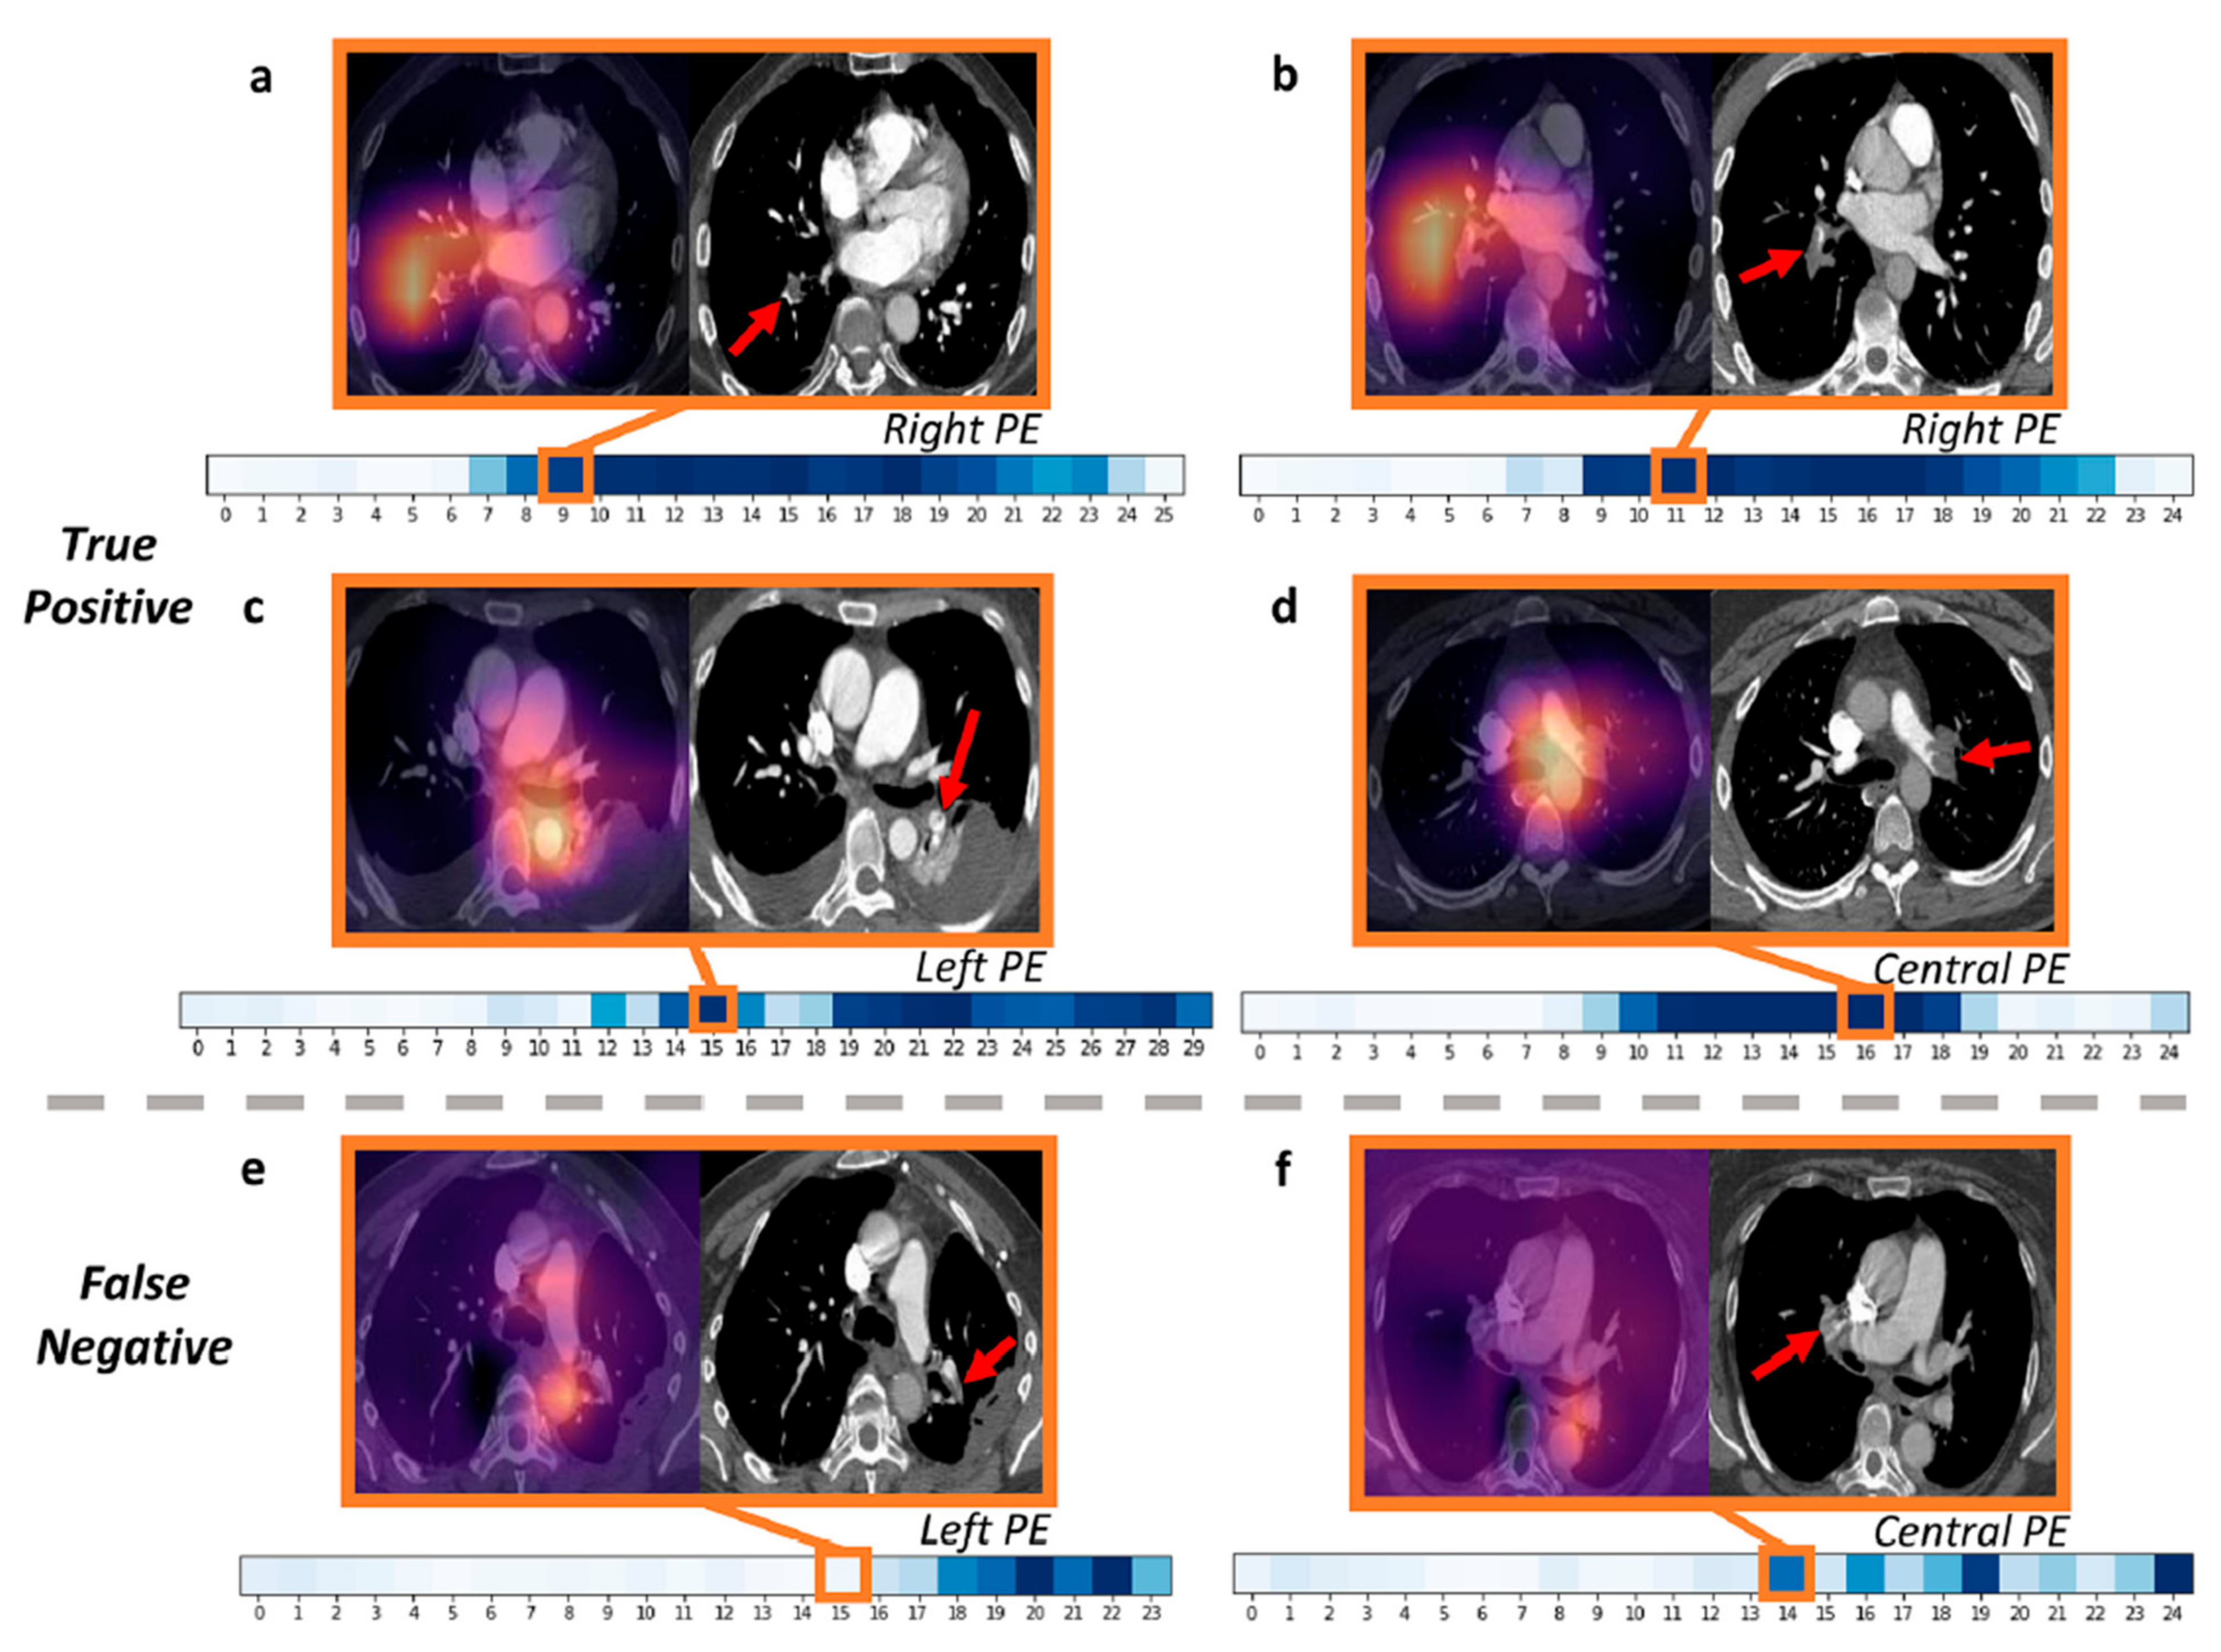

- Soffer, S.; Klang, E.; Shimon, O.; Barash, Y.; Cahan, N.; Greenspana, H.; Konen, E. Deep learning for pulmonary embolism detection on computed tomography pulmonary angiogram: A systematic review and meta-analysis. Sci. Rep. 2021, 11, 15814. [Google Scholar] [CrossRef]

- Huhtanen, H.; Nyman, M.; Mohsen, T.; Virkki, A.; Karlsson, A.; Hirvonen, J. Automated detection of pulmonary embolism from CT-angiograms using deep learning. BMC Med. Imaging 2022, 22, 43. [Google Scholar] [CrossRef]

- Ma, X.; Ferguson, E.C.; Jiang, X.; Savitz, S.I.; Shams, S. A multitask deep learning approach for pulmonary embolism detection and identification. Sci. Rep. 2022, 12, 13087. [Google Scholar] [CrossRef] [PubMed]

- Grenier, P.A.; Ayobi, A.; Quenet, S.; Tassy, M.; Marx, M.; Chow, D.S.; Weinberg, B.D.; Chang, P.D.; Chaibi, Y. Deep Learning-Based Algorithm for Automatic Detection of Pulmonary Embolism in Chest CT Angiograms. Diagnostics 2023, 13, 1324. [Google Scholar] [CrossRef] [PubMed]